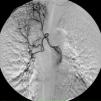

On the seventh day, a new episode of massive hemoptysis took place. On this occasion, the patient was hemodynamically unstable and the laboratory tests disclosed a hemoglobin of 7.3g/dL. Two units of “packed” red blood cells and sufficient volume of crystalloid fluid were administered. The patient refused another bronchoscopy. Urgent bronchial arteriography was performed. Selective catheterisation of the right intercostobronchial trunk showed features of marked hypervascularization, including a tortuous and dilated right bronchial artery and bronchial-to-pulmonary retrograde shunts in the right apex (Fig. 1). Selective catheterisation of the left bronchial artery showed a bronchovascular fistula, where contrast leaked from the blood vessel drawing the left bronchial tree bronchography (Fig. 2, panel A), and a tortuous and dilated superior division of left bronchial artery too (Fig. 2, panel B). Immediate cessation of hemoptysis was obtained after embolization of the bronchovascular fistula and the right intercostobronchial trunk with polyvinyl alcohol microspheres of 700–900μm until complete stasis of the artery. Following the procedure, the patient was stabilized hemodynamically and did not present new episodes of hemoptysis. After the last episode, the patient stopped smoking and she has remained asymptomatic until now.

Left bronchial arteriography. Panel A. Circle: bronchovascular fistula. Panel B. Black arrow: Fistula formation between a vessel and the tracheobronchial tree. White arrows: contrast leakage from the vessel drawing the bronchial tree bronchography. Circle: tortuous and dilated superior division of left bronchial artery.